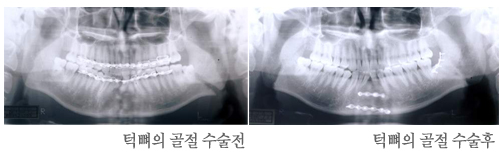

ÅÎ »À´Â ¾È¸é°ñ Áß °¡Àå °ÇÏÁö¸¸ ÇϺο¡ µ¹ÃâÇØ ÀÖÀ¸¸ç ¸î ±ºµ¥ ¾àÇÑ °÷ÀÌ ÀÖ¾î °ñÀýµÇ´Â ºóµµ°¡ ³ô½À´Ï´Ù. ±³Åë»ç°íÀÇ °æ¿ì ´ë°³ ½ÉÇÑ ´Ù¹ß¼º ¼Õ»óÀÇ °æ¿ì ÇÔ²² ¹ß°ßµÇ´Â °æ¿ì°¡ ¸¹½À´Ï´Ù. ƯÈ÷ ¿ÀÅä¹ÙÀÌ »ç°íÀÎ °æ¿ì ÀÚÁÖ Á¢ÇÏ°Ô µÇ°í »óÇØÀÇ °æ¿ì¿Í ´Ù¸£°Ô °³¹æ¼º °ñÀýÀÎ °æ¿ìµµ ÈçÇÕ´Ï´Ù.

ÅÎ »À°¡ °ñÀýµÇ¸é ±× ÁÖº¯ºÎ¿¡ µ¿Åë, ºÎÁ¾, ¹Ý»ó ÃâÇ÷, ÃâÇ÷, °³±¸ Àå¾Ö, ±³ÇÕ ºÎÀü, ÀÔÀ» ¹ú¸± ¶§ ÅÎÀÌ ÇÑÂÊÀ¸·Î Ä¡¿ìÃÄÁü, ħÈ긲, ¾ÐÅë, ¿¬¹ßÀ½ µîÀÌ ÀÖ½À´Ï´Ù.

¿ì¼± ±âµµ¸¦ È®º¸ÇÏ°í °ñÀýÀÌ °æ¹ÌÇÑ °æ¿ì¿¡´Â ºñ°üÇ÷Àû ¹æ¹ýÀ¸·Î Á¤º¹ ÈÄ 6-8ÁÖ°£ Barton ºØ´ë¹ý, Ä¡°£ ö¼± °á¹Ú, ¾Ç°£°íÁ¤ µîÀ¸·Î °íÁ¤À» ÇØ ÁÖ¾î¾ß ÇÕ´Ï´Ù.

ÇÏÁö¸¸, ¾Ç°£°íÁ¤À» 1ÁÖ °£À̳ª ÇØ Á־ Á¤º¹µÇÁö ¾Ê°Å³ª ´Ù¹ß¼º °ñÀý ¶Ç´Â ºÒ·® °ñÀýÀ̰ųª ±¸°°ú ÅëÇÏ´Â °æ¿ì, °ñÀýºÎÀ§¿¡ º¯À§°¡ ½ÉÇÑ °æ¿ì, ¿À·¡µÈ °ñÀý, ¸¹Àº Ä¡¾Æ°¡ °á¼ÕµÈ °æ¿ì µîÀº °üÇ÷Àû Á¤º¹¼úÀ» ½ÃÇàÇÏ¿©¾ß ÇÕ´Ï´Ù.